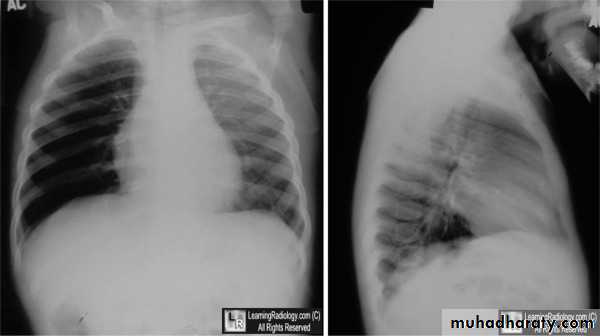

CXR : expiratory or lateral decubitus , reveal the presence of radiopaque objects and can also identify focal air trapping.Bronchoscopy.

Expiratory chest radiograph in a 12-month-old boy with a 2-month history of wheezing demonstrates continued hyperlucency and hyperexpansion of the right hemithorax.